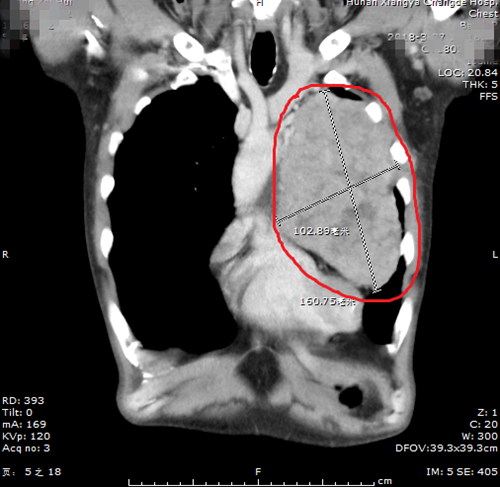

今年52岁的黄大叔,性格开朗、热情好客,20岁时就开始饮酒,亲朋好友相聚时就会一起开怀畅饮。 就在五年前,一次聚会上,黄大叔“喝高了”,第2天早上醒来发现右侧眼睑居然睁不...